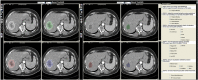

Methods: Image texture analysis is an approach of quantifying heterogeneity that may not be appreciated by the naked eye. Different methods can be applied including statistical-, model-, and transform-based methods.

Results: Early evidence suggests that texture analysis has the potential to augment diagnosis and characterization as well as improve tumor staging and therapy response assessment in oncological practice.

Conclusion: This review provides an overview of the application of texture analysis with different imaging modalities, CT, MRI, and PET, to date and describes the technical challenges that have limited its widespread clinical implementation so far. With further efforts to refine its application, image texture analysis has the potential to develop into a valuable clinical tool for oncologic imaging. TEACHING POINTS : • Tumor spatial heterogeneity is an important prognostic factor. • Image texture analysis is an approach of quantifying heterogeneity. • Different methods can be applied, including statistical-, model-, and transform-based methods. • Texture analysis could improve the diagnosis, tumor staging, and therapy response assessment.